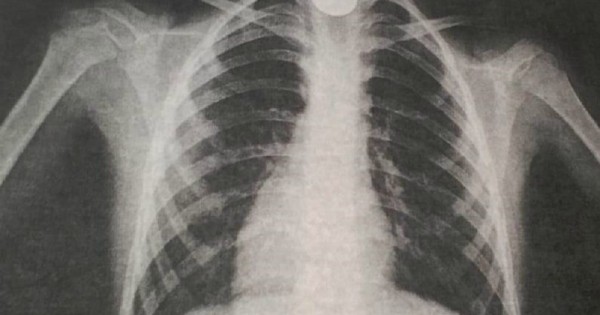

بەلگىلى بولعانداي, ويناپ وتىرعان 9 جاستاعى بالا بايقاماي تيىندى جۇتىپ قويعان. ءبىر ساعاتتان سوڭ ونىڭ تىنىس الۋى قيىنداپ, جاعدايى ناشارلاعان. بۇدان سوڭ, ول وبلىستىق كوپبەيىندى بالالار اۋرۋحاناسىنا جەتكىزىلگەن. وكپە جاسۋشالارىن تۇسىرگەن رەنتگەنوگرافيا قورىتىندىسى وڭەشتىڭ جوعارعى جاعىندا بوگدە زاتتىڭ تۇرعاندىعىن انىقتاعان.